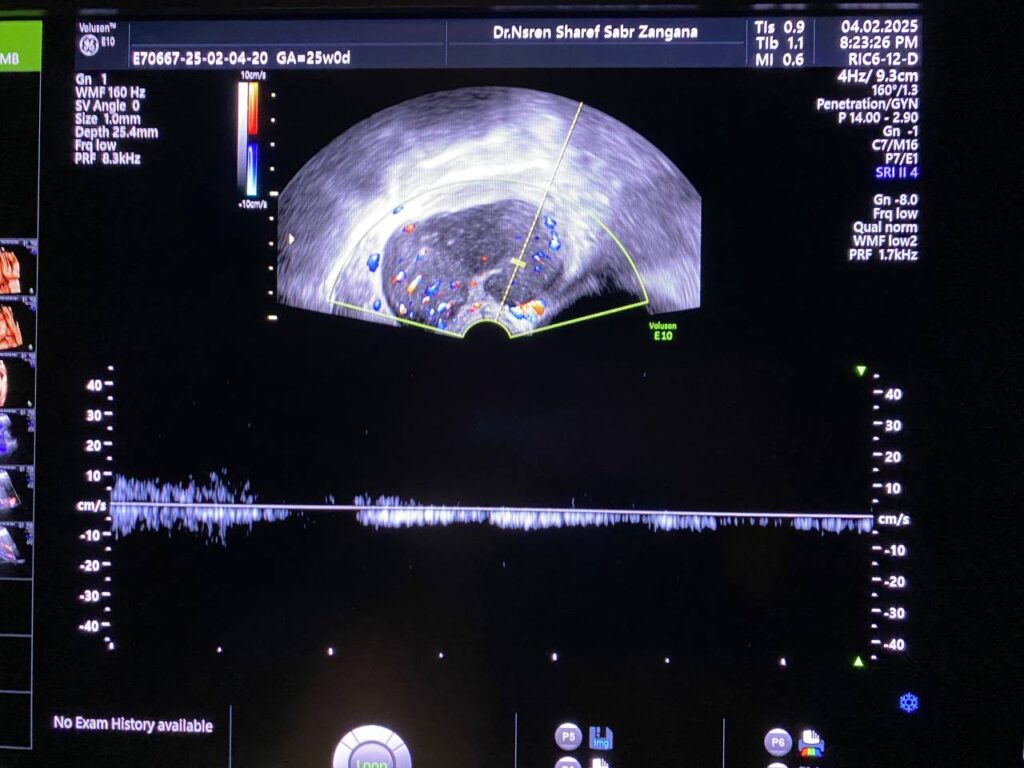

Associated with Presence of pathological lymph node in the right para iliac region size 35x24mm& other pathological lymph node in the left para iliac region 35x21mm , lymphoma or secondary metastasis can not be excluded